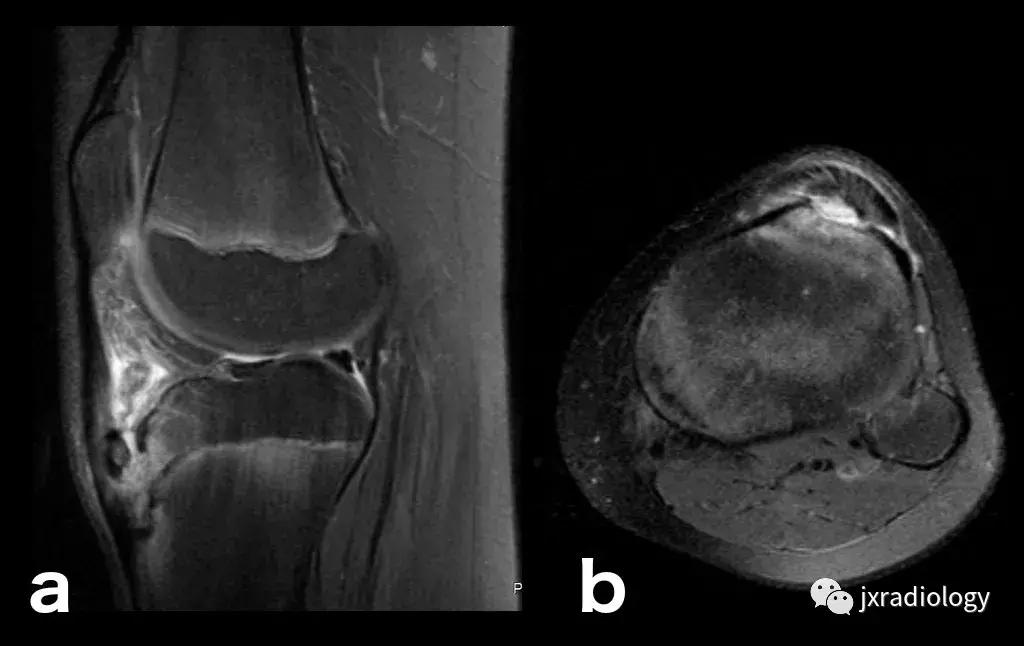

图21:这名患者的炎症性关节炎表现为围绕内侧股 - 胫室侵蚀性改变的骨髓水肿。它是血管源性骨髓水肿的一个例子(继发于血液和血清传递至骨髓空间毛细血管床)(a,b:冠状T1-WI和PD-FS-WI)。

图22:骨肉瘤(a,b:冠状和轴向PD-FS-WI):肿瘤性水肿继发于骨小梁破坏引起的直接毛细血管损伤,并伴有血管内液体释放和出血。区分周围水肿和肿瘤侵袭可能是困难的。

图23:骨巨细胞瘤(PD-FS-WI):也存在肿瘤性骨髓水肿。